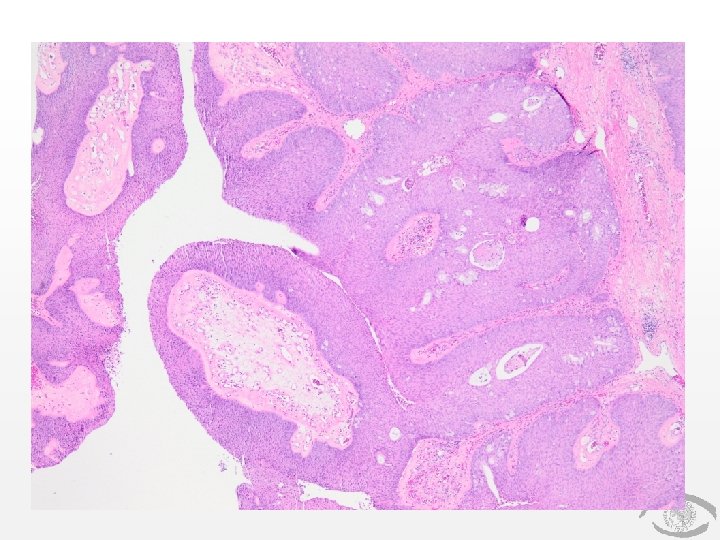

Discussion: Sinonasal Papilloma “Schneiderian Papilloma” Benign epithelial tumor with 3 morphological features: 1. 2. 3. Exophytic (fungiform, septal, squamous) Oncocytic (“Cylindrical”) Inverted (most common, ~70%) Can be further broken down histologically (mixed, squamous, junctional)

Copyrights apply